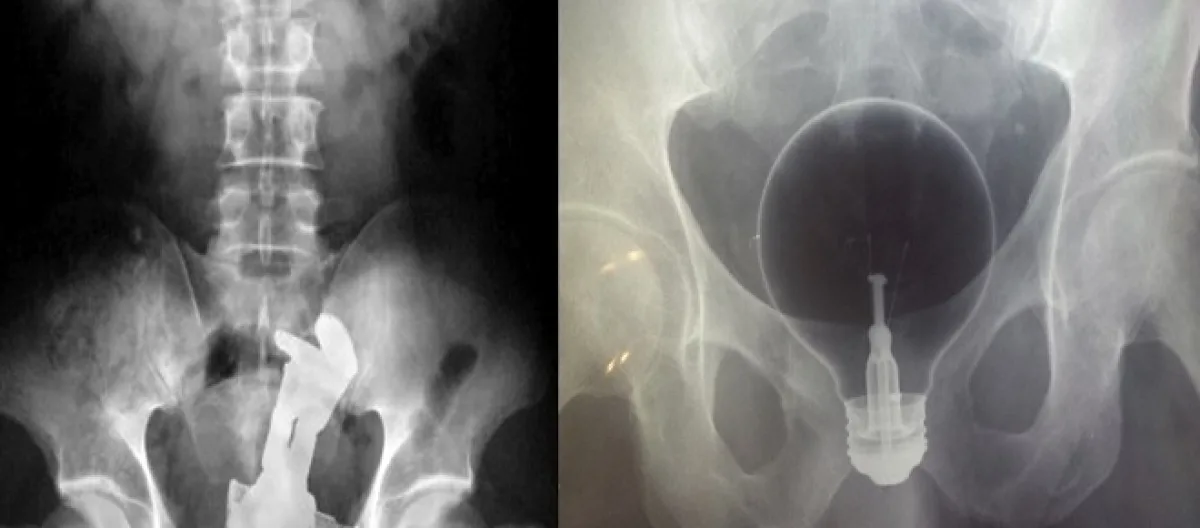

Muitas vezes, o paciente chega ao hospital com dores, mas não tem coragem de contar o motivo pelo qual as dores acontecem, daí somente fazendo um raio-X para que o médico entenda a situação.

7- Um vibrador “perdido” e uma pinça para tentar retirar o vibrador, que também acabou se perdendo.